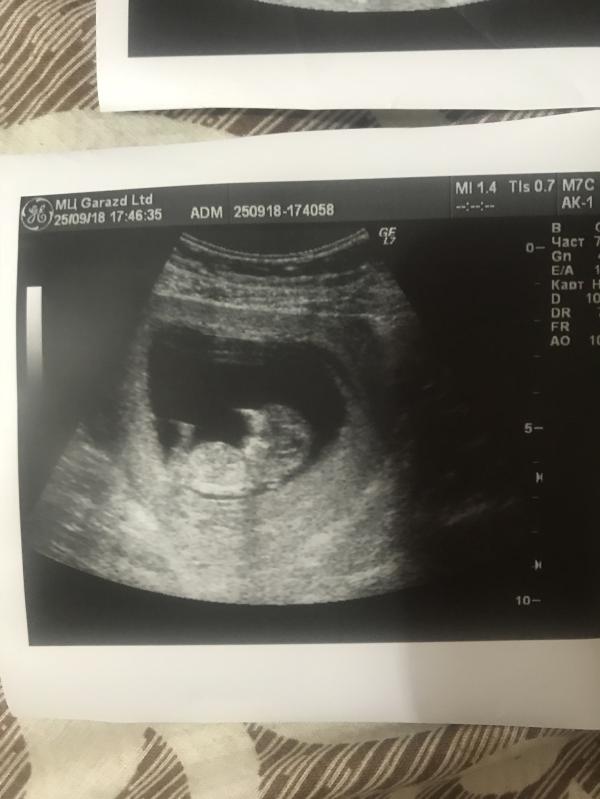

Или кидайте те кто ещё не знает пол, вместе поразмышляем 😁 вот наш ☺️

@evgenia_ps, по половому бугорку вроде видно , если конечно он там где я думаю 🙈 я ж такой « эксперт» 😅 вот на своём УЗИ девочку вижу 🙈 ну или очень хочу видеть 😁

Ну у вас этот бугорок паралельно позвоночнику, такое обычно у девочек) у нас на УЗИ торчал под 45 градусов, и будет мальчик.

Но это вероятность 90% на таком сроке как у вас.